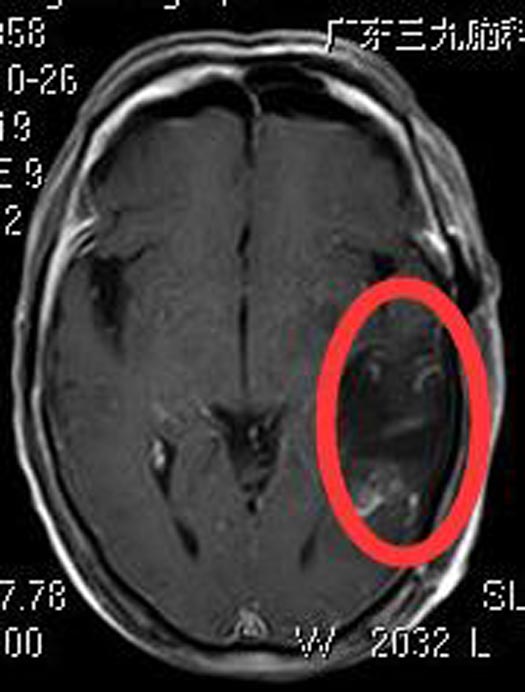

了解病情后,潘爷爷要求手术治疗。考虑患者高龄,综合神经外科会同麻醉科等相关科室进行会诊,制定了术中、术后各种突发意外处置详细预案。由鲁明主任主刀,在唤醒麻醉下行左侧颞叶占位切除术,术中顺利唤醒,遵嘱动作良好,镜下见灰白色肿瘤,质软、血供丰富,导航定位肿瘤范围后,荧光显微镜下全切肿瘤,手术顺利,患者语言、肢体功能完好,术后无功能障碍,康复出院。

术后